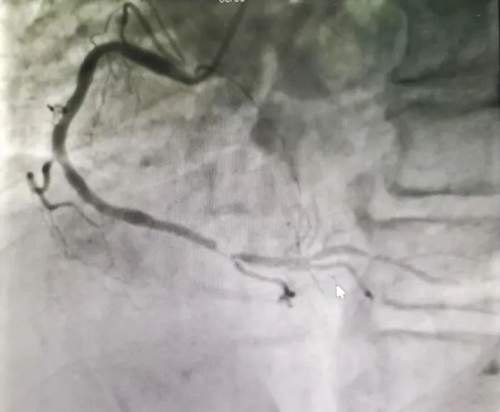

急診冠脈造影顯示RCA近段閉塞,立即送入指引導(dǎo)絲順利通過閉塞病變,恢復(fù)3級血流。

立即加壓輸液并給予多巴胺、阿托品靜脈應(yīng)用,約10分鐘后血壓逐漸恢復(fù)正常,未再出現(xiàn)室性逸搏心律,生命體征逐漸平穩(wěn)后,于閉塞病變成功植入2枚支架,血流TIMI3級,生命體征平穩(wěn),送回病房進一步診治。